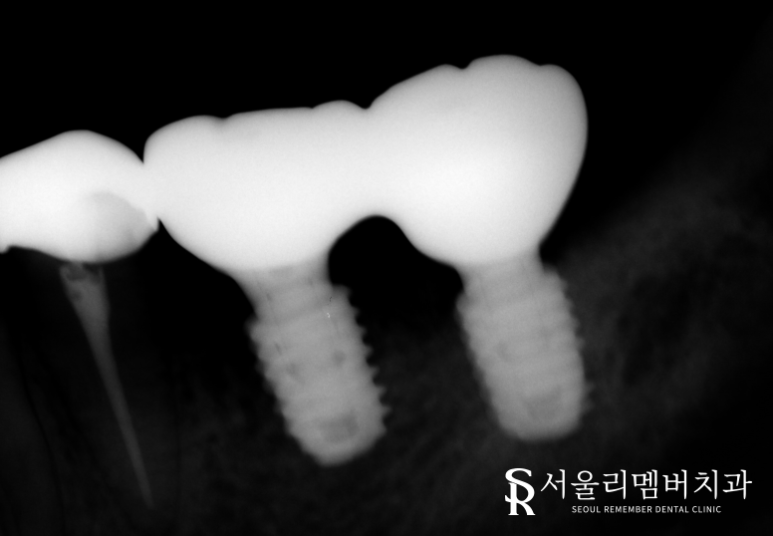

이후 신대방 치과 에서는 골융합을 확인하고 나서

보철을 올려드리기로 했죠.

몇 달이 지나고 튼튼하게 고정되어 있는

픽스쳐를 확인한 뒤에 최종 크라운을 올려드렸습니다.

이전과는 달리 단단한 픽스쳐가

치조골 속에 고정이 잘 되어 있었으며,